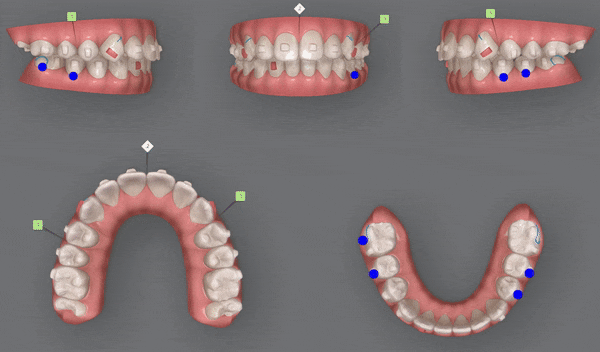

3rd(25개)

인비절라인의 또 다른 장점 중 하나는

악궁 확장에 상당히 효과적인 기능을 가지고 있습니다.

공간이 부족하면 발치교정을 해야 했던 이전과는 달리

특수강화 플라스틱 재질인 인비절라인은

치아를 안쪽과 바깥쪽에서 적은 힘으로 지속적으로 잡아주기 때문에

거의 통증없이 악궁을 확장시켜 치아이동에 관여합니다.

4th(14개)

마지막으로 섬세한 디테일링을 위해

네번째 클린체크

(총 14개의 장치)를 진행해드렸습니다.

소아인비절라인

어린이인비절라인

중학생인비절라인

청소년인비절라인

유펜바른치과에서는

이전의 클린체크와는 어태치먼트의 모양과 위치가

달라져

이전의 클린체크를 보완해 교정치료의 완성도를 높여 줍니다.